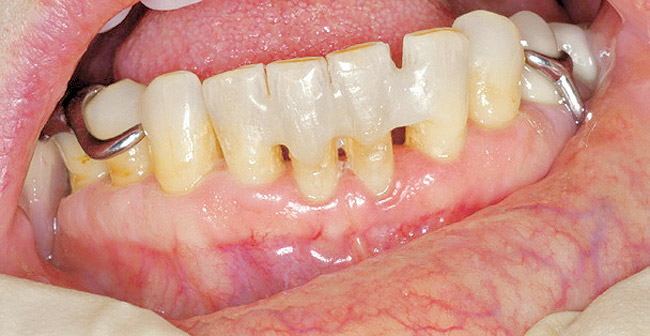

Figure 12  Facial view of composite splint.

Figure 12

Under the sextant approach, one quadrant is treated and the patient is left to heal for 2 months before proceeding to any additional quadrants. While the patient heals, a 10-day course of antibiotics and 2 months of twice-daily chlorhexidine rinsing may be prescribed. Figure 4 shows a patient who was taking oral bisphosphonates for 3 years and was treated with the sextant approach. As seen in the radiograph, the patient has one molar in the lower right quadrant. This tooth was extracted and the patient was given 2 months to heal (Figure 5 and Figure 6). The patient was placed on antibiotics and chlorhexidine rinse. After 2 months, no signs of BRONJ were observed, and the anterior teeth were scheduled for extraction. They were extracted as atraumatically as possible, and the site was sutured (Figure 7 and Figure 8).The patient then was given another 2 months to heal, following the previous protocol. After 2 months of healing, no BRONJ was observed (Figure 9).

Then, patient was able to move forward with the prosthesis. Figure 10 shows a periodontal patient who was taking oral bisphosphonates for osteoporosis. The patient had full-mouth scaling and root planing, then was given 2 months to heal and instructed to rinse with chlorhexidine twice daily. After no signs of BRONJ were observed, the patient had full-mouth osseous surgery on her few remaining teeth in the mandible. The surgery was performed all at once and not according to the sextant approach because the patient was on a heart and lung transplant list and was moved up the list while healing from the scaling and root planing. The patient also had extensive bone loss in her anterior mandible (Figure 11).To avoid performing extractions, a simple composite splint was placed between the partial dentures (Figure 12 and Figure 13). The splint reduced the mobility of the teeth and made them less likely to be knocked out during any surgical intubation procedure.